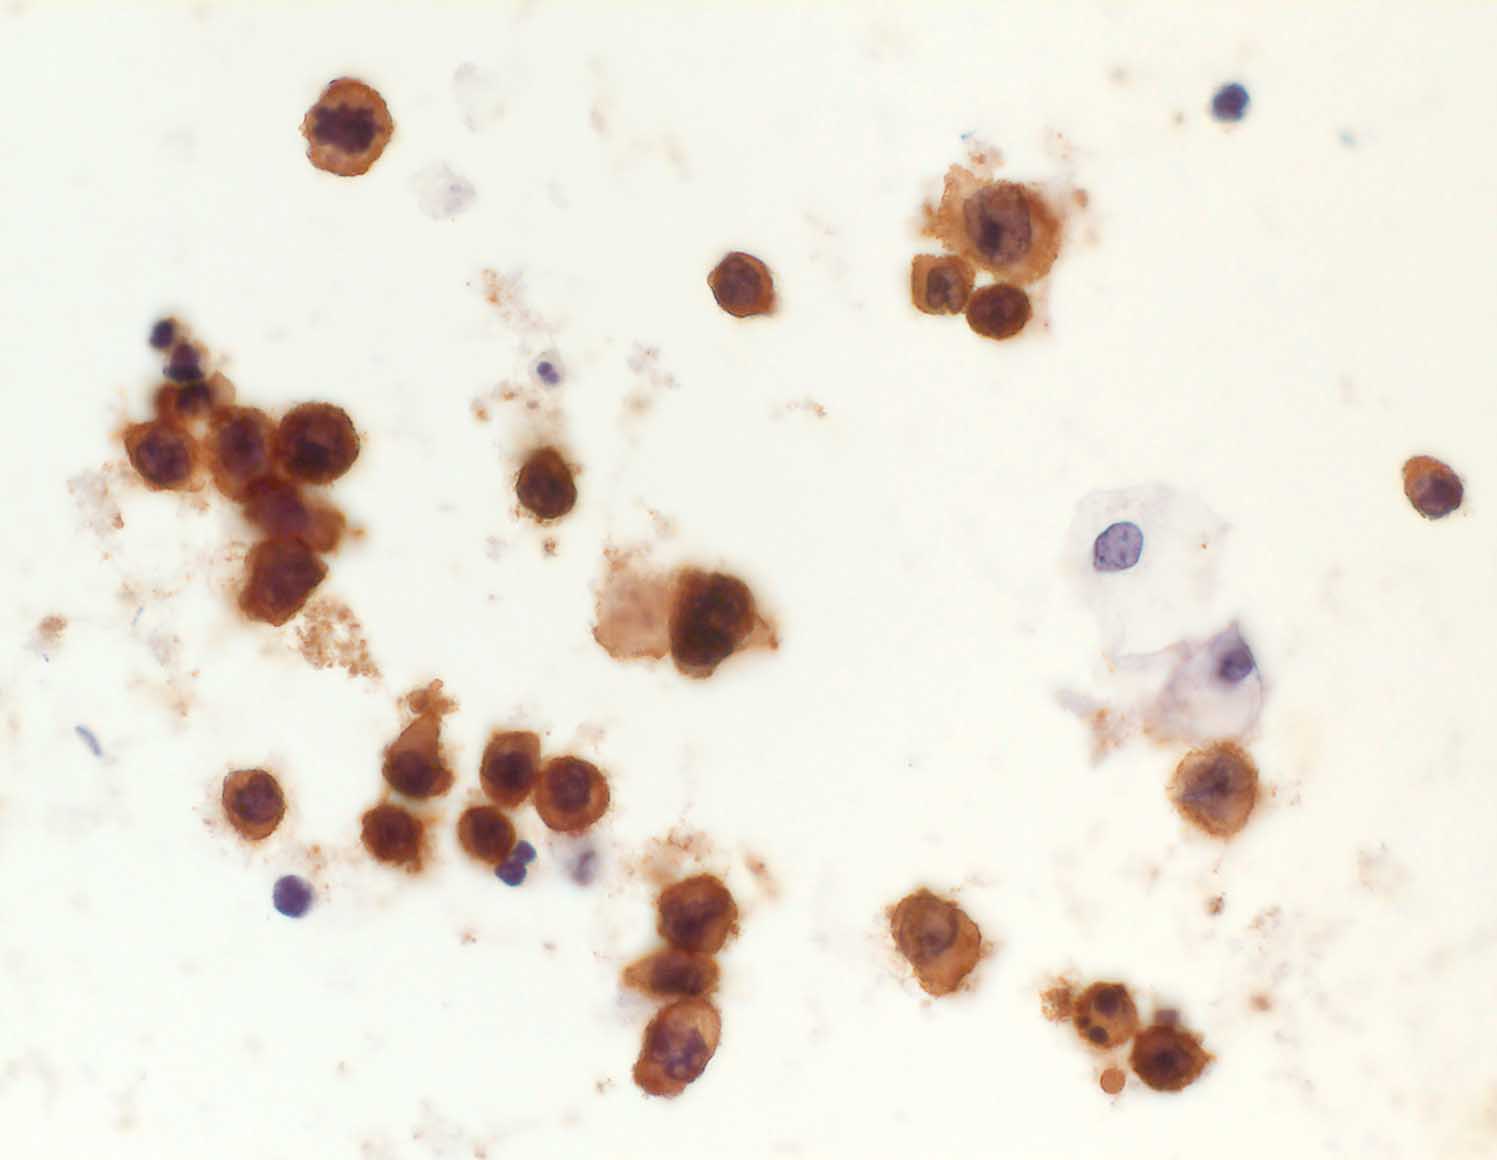

Diagnostischer Nutzen:

Abgrenzung von Lymphomen von anderen kleinen blauen und rundzelligen Tumoren Unterscheidung von kleinzelligen Karzinomen und Lymphomen